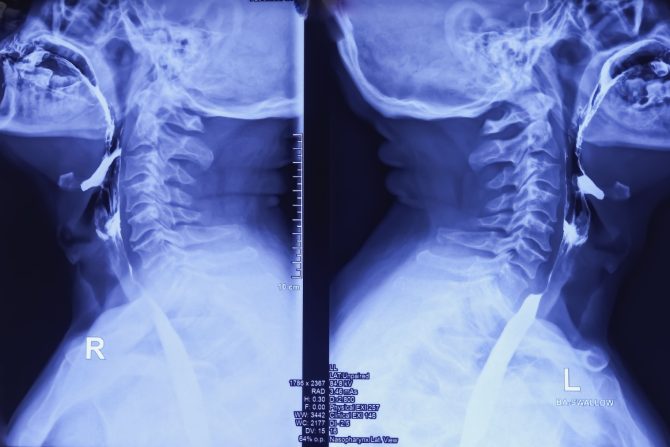

Kontrastna ezofagografija je rendgenološka metoda kojom se pregleda jednjak uz pomoć kontastnog sredstva i tako prikazuje položaj jednjaka, njegova peristaltika, reljef sluznice i njegov odnos prema susednim organima

Kontrastna ezofagografija ne prikazuje samo statične slike, već stvara video snimak jednjaka tokom procesa gutanja, čime omogućava otkrivanje različitih poremećaja, kao što su čirevi, tumori, blokade, polipi, zapaljenja i druge promene tkiva. Za ovu metodu pregleda potrebno je koristiti kontrastno sredstvo kao što je barijum ili jodno kontrastno sredstvo. Barijum je beli prah koji se često meša sa vodom kako bi se napravio gusti napitak. Kada se proguta ova tečnost oblaže unutrašnjost jednjaka. Barijum apsorbuje rendgenske zrake i prikazuje se svetlom bojom na rendgenskom snimku.

Kada pacijenti dođu na pregled potrebno je da skinu odeću i nakit sa područja vrata i grudnog koša i da se naslone na rendgenski sto. Pregled počinje u stojećem stavu. Pacijent čašu sa barijumom drži u levoj ruci i uzma gutljaj koji zadržava u ustima i čeka na komandu “progutajte” od strane zdravstvenog radnika. Lekar može tražiti da se pacijent okreće na levi ili desni bok, kao i da u jednom trenutku u toku pregleda legne. Procedura traje najviše pola sata, ali često i kraće.